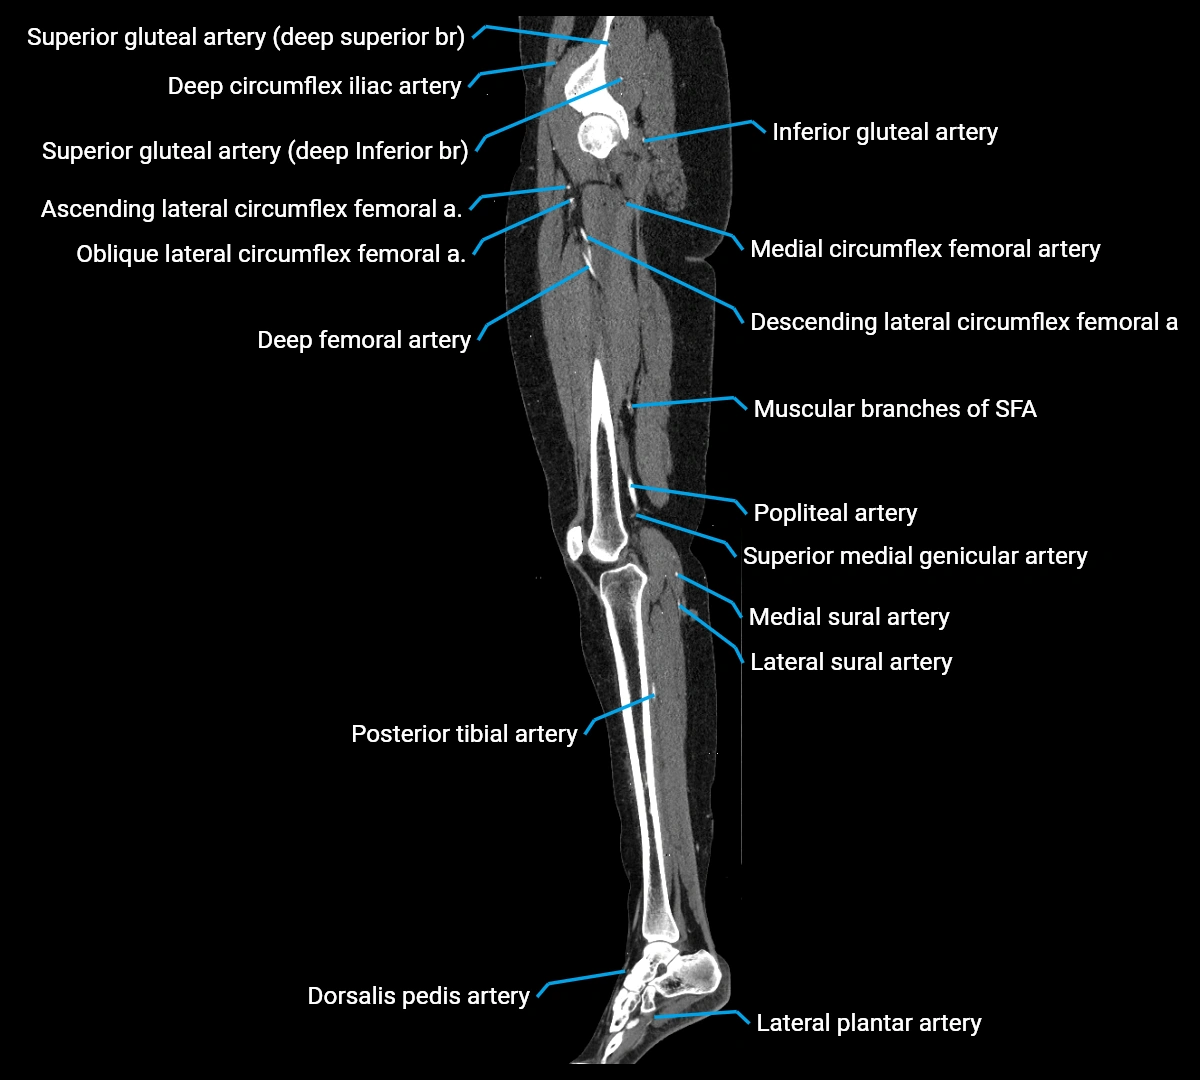

Contrast-enhanced CT (CTA):

• Gold standard for abdominal aortic imaging

• Provides excellent detail of lumen, wall, aneurysm, thrombus, and branch vessels

• Multiplanar and 3D reconstructions help in aneurysm measurement, stent graft planning, and dissection evaluation

• Detects acute rupture, traumatic injury, or occlusion with high sensitivity